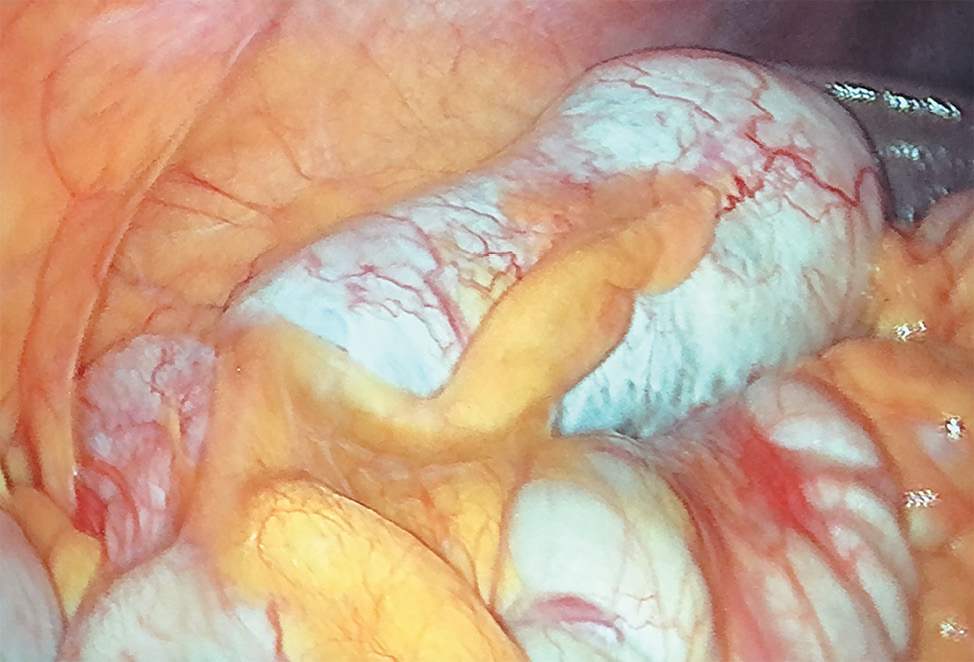

On March 7, 2020, a CT scan of the abdominal organs was conducted, and a 137 × 60 × 58 mm formation was found in the loops of the small intestine. The growth from its wall on the right side of the abdomen, clearly separated from the surrounding structures, has a heterogene structure, and the fiber around the formation is slightly compacted (Fig. 1).

Fig. 1. Spiral CT picture of abdominal organs with contrast (arrows indicate a pathological formation)